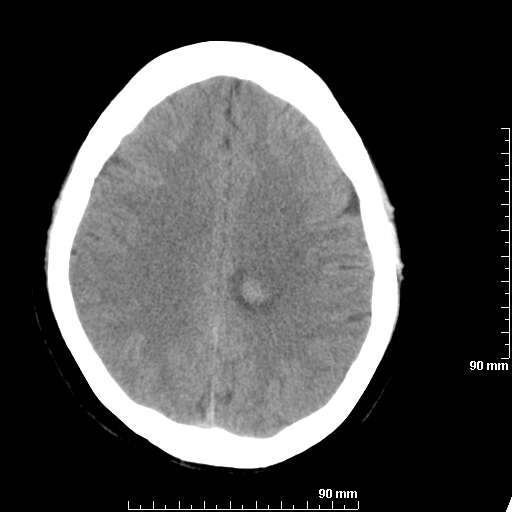

我院西门子单排CT由于一零件受损而产生的伪影.

哈哈,都不是。是虑线器fiter裂损。大家没想到吧。

哦,跟脑出血有点像哦

形状不规则,边缘模糊。比较特殊的一种伪影哈!

这种伪影很常见!伪影应该是在视野的中心的。

西门子的虑线器fiter裂损这才是很难见的问题,GE的最常见

虑线器老化,中间崩裂一块掉了